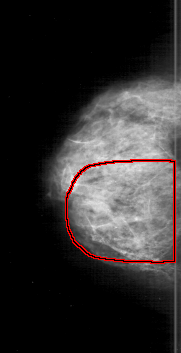

D_4192_1.RIGHT_MLO

RIGHT_MLO LINES 5971 PIXELS_PER_LINE 3346 BITS_PER_PIXEL 12 RESOLUTION 43.5 OVERLAY

FILE: D_4192_1.RIGHT_MLO.OVERLAY

TOTAL_ABNORMALITIES 1

ABNORMALITY 1

LESION_TYPE CALCIFICATION TYPE AMORPHOUS-PLEOMORPHIC DISTRIBUTION REGIONAL

ASSESSMENT 5

SUBTLETY 5

PATHOLOGY MALIGNANT

TOTAL_OUTLINES 1

BOUNDARY